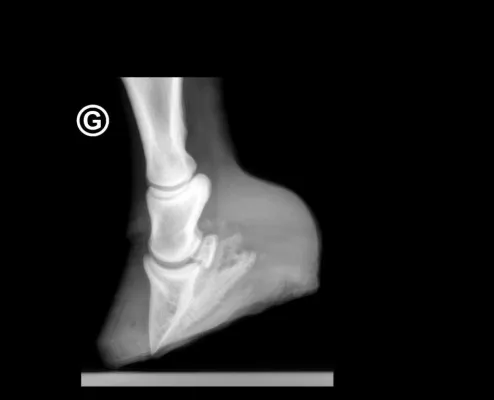

Bild: Achtung Pferdebesitzer: Die Problematik von frisch geerntetem Heu und Gras – Hufrehegefahr

Es ist unschwer abzusehen, was eine solche Mischung von „Pferdefutter“ in einem Pferdemagen auslösen kann. Gaskoliken – aufgrund der explosionsartigen Vermehrung der angesprochenen Bakterien und Keime im Magen/Darmtrakt des Pferdes - können die Folge sein. Nicht selten führt dieses Unverständnis zum Tod eines Pferdes. Wir geben ferner zu bedenken, dass eine solche Kolik – sofern das Pferd die ganze Tortur überlebt - letztendlich auch zu einer Hufrehe führen kann. Eine für jede Equidenart lebensbedrohliche Situation!